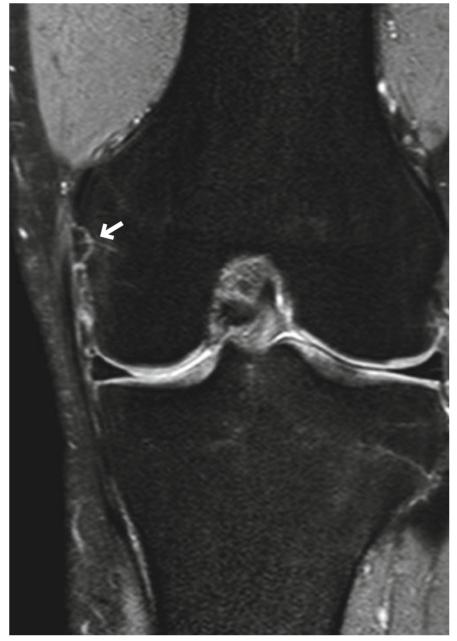

图5.9 3级撕裂(完全撕裂)。一个十八九岁的男性。(a)冠状T2*WI和(b)关节镜图像显示MCL近端部分完全撕裂(箭头),周围有水肿改变。在(b)中,关节囊的破裂(MCL的深层,箭头)可见。注意撕裂的半月板股韧带(MCL深层,a中箭头所示)